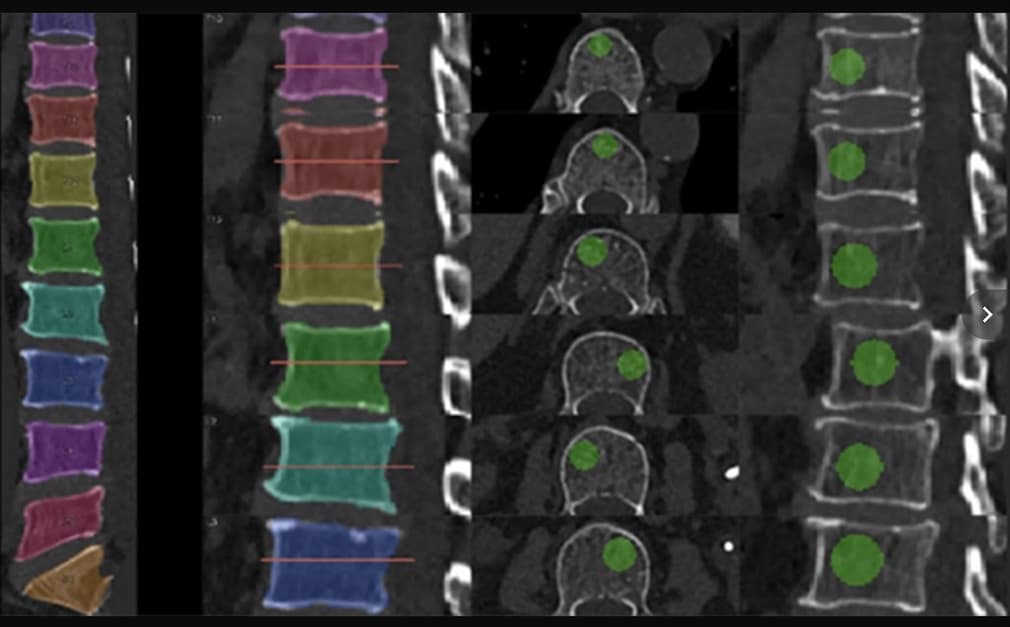

La tomodensitométrie quantitative serait une bonne alternative à l’ostéodensitométrie pour le dépistage de la fracture par déminéralisation osseuse. Pour gagner en précision dans l’évaluation de la DMO par TDM, une étude introduit le deep learning afin de définir une norme d’atténuation trabéculaire...